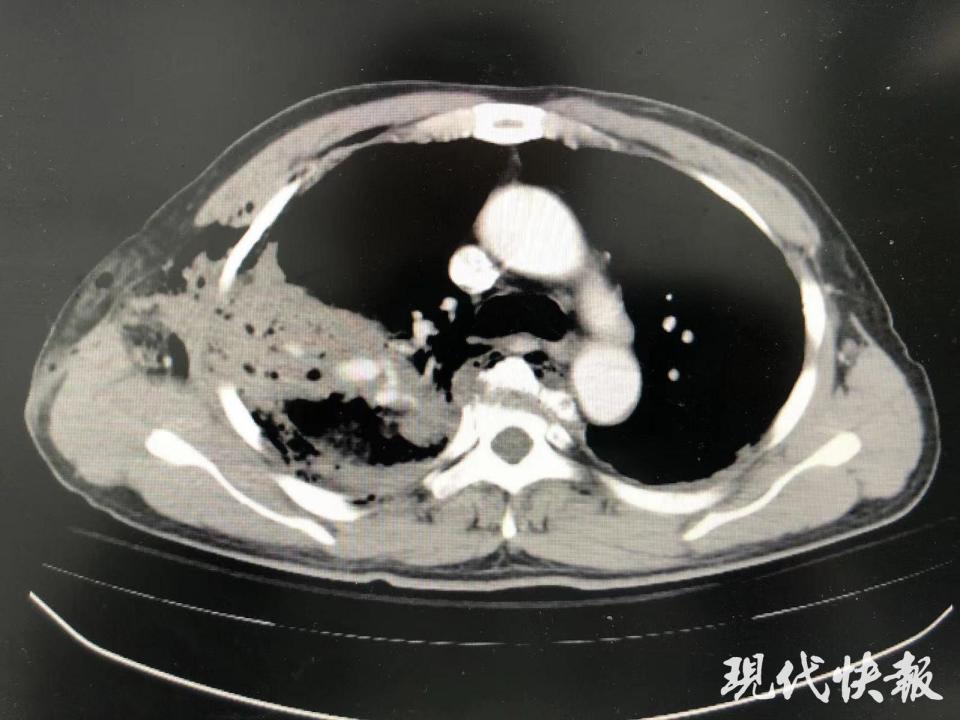

“我们急诊进行CT检查,从影像学上观察,右侧整个胸腔被贯穿,贯穿伤距离主动脉只有5毫米,真的是命悬一线。整个手术历时3小时35分钟,术中出血约3000毫升,幸运的是,钢筋没有伤到大血管,如果伤到大血管又在现场被拔出来,这个出血量不可估计。”俞建荣说。